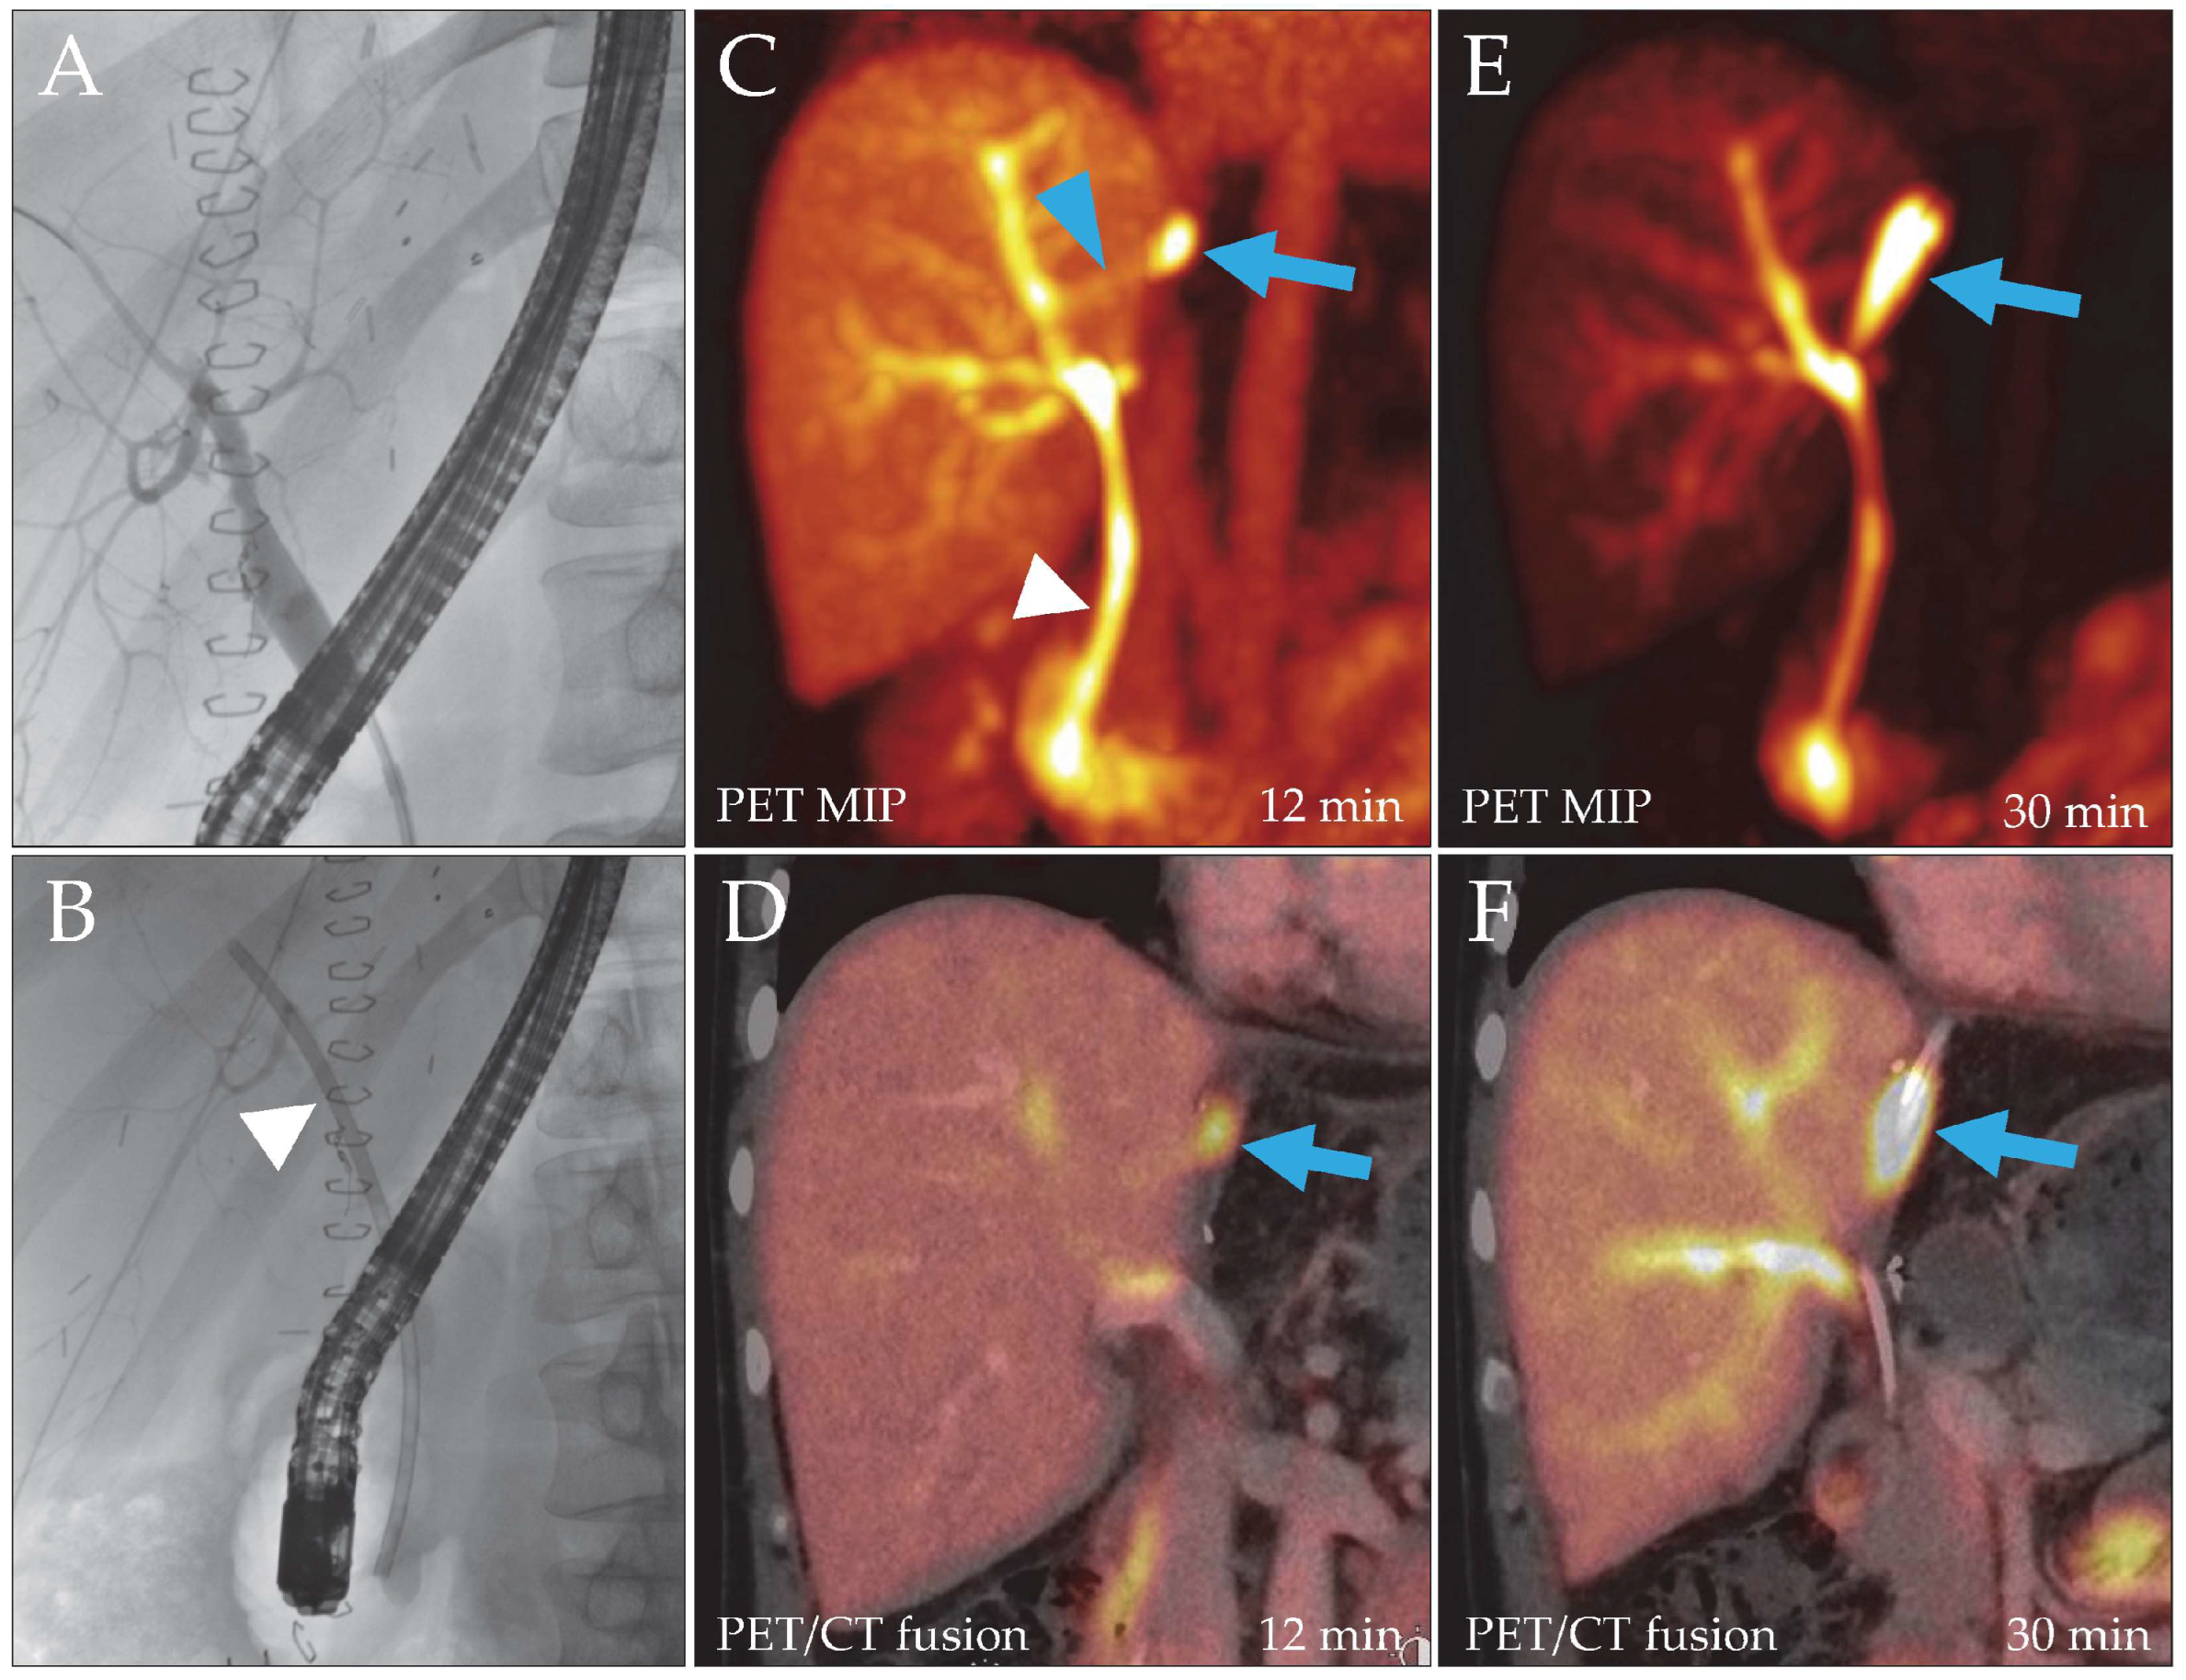

Figure 1. Patient 2, liver recipient. Post-transplantation ERC (A) did not reveal a bile leak, but to facilitate biliary drainage, a hepatoenteric stent was placed ((B), arrowhead). Due to persistent drainage of bile through the catheter, a DAZA-PET/CT was performed. Despite a patent stent ((C), white arrowhead), it showed a leakage site at the liver resection surface from 12 min after tracer injection ((C,D), blue arrow; SUVmax 29.7/SUVmax/mean liver tissue 9.9/7.8) draining into a bilioma, which filled over time ((E,F), blue arrows). A small bile duct branch appeared to reach the leak from the main right hepatic ducts ((C), blue arrowhead). MIP, maximum intensity projection.